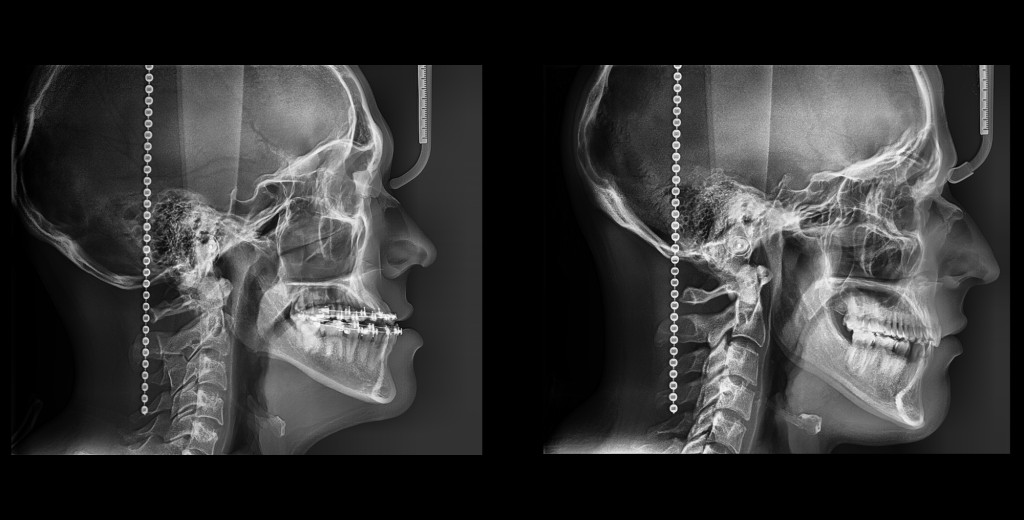

CEFALOMETRIA FULL LATERAL

• Toda la información en una sola imagen

• Es una versión más amplia del cefalograma tradicional

Y si una Imagen más amplia pudiera revelar posturas,

patrones respiratorios y potenciales disfunciones

¿La elegirías?